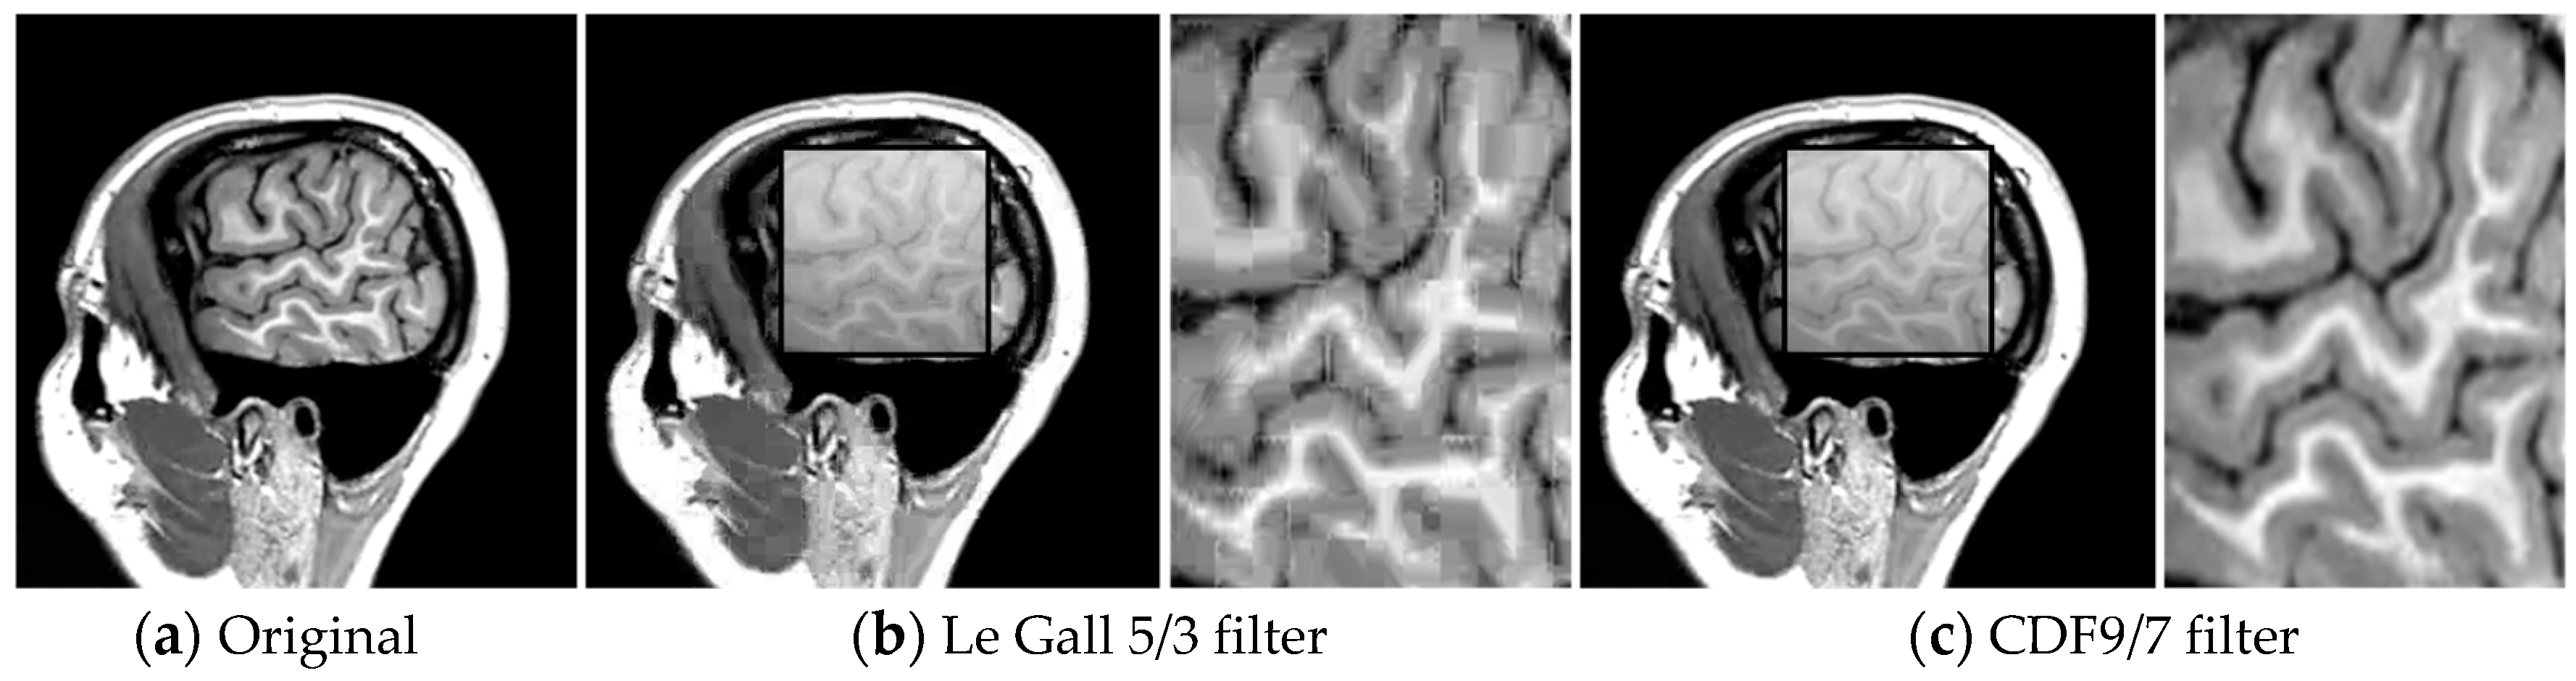

By a subjective quality assessment of images shown in Figure 8, we opt for CDF 9/7, which reduces the level of artifacts. Indeed, the obtained results show that the recovered frame using the bandelet algorithm + SPIHT is close to the original frame.

Figure 8.

Recovered frames using: (b) Bandelet (Le Gall 5/3)-SPIHT and (c) Bandelet (CDF9/7)-SPIHT at 0.2 Mbps.

It is worth noting the presence of blurred areas in the image when Le Gall 5/3 filters are used.

From these results, illustrated by some examples in Figure 8, Figure 9 and Figure 10, we can draw three conclusions:

- 1

- The performance of bandelet-SPIHT algorithm is superior to that of SPIHT (wavelet-based).

- 2

- Bandelet-SPIHT is able to capture complex geometric contents of images and surfaces and reduce drastically existing redundancy in video while classical SPIHT (based on discrete wavelet transform) is subject to artifacts.

- 3

- The bandelet-SPIHT algorithm gives better results in the case of CDF 9/7 wavelet filters than in the case of Le Gall 5/3.